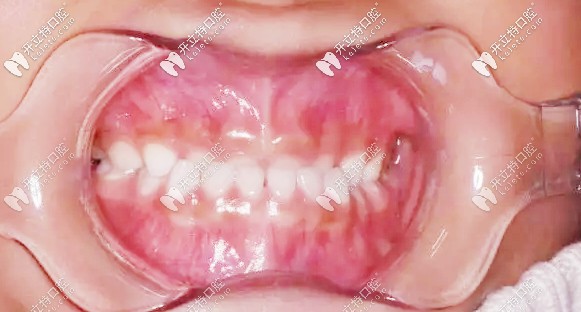

第二次復(fù)診,孩子的牙齒改善很明顯,我這顆懸著的心也算是能稍稍放下了▼

二次復(fù)診牙齒狀況